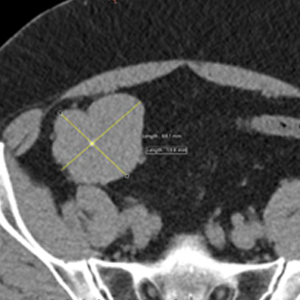

Caso 2 | Abril 2026 | Hospital Italiano

Masculino. 73 años. MC: Dolor unilateral en miembro inferior izquierdo de larga evolución (2 meses) que empeora los últimos días. […]